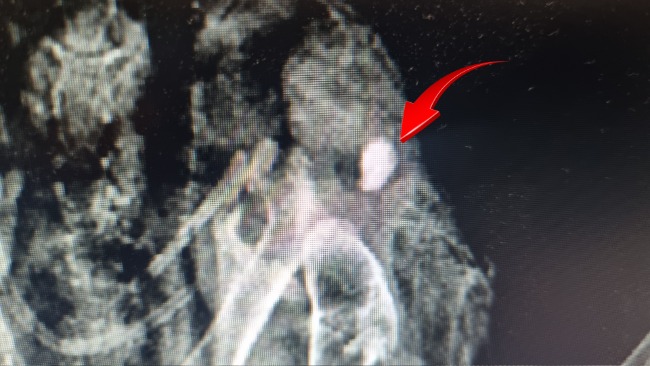

Właściciela posesji miała rację - ptak ma w sobie świeży śrut, który rozerwał mu jedno skrzydło, które jest całkowicie połamane. Dobrze się przyglądając, można zobaczyć ranę wlotową 😭😭😭